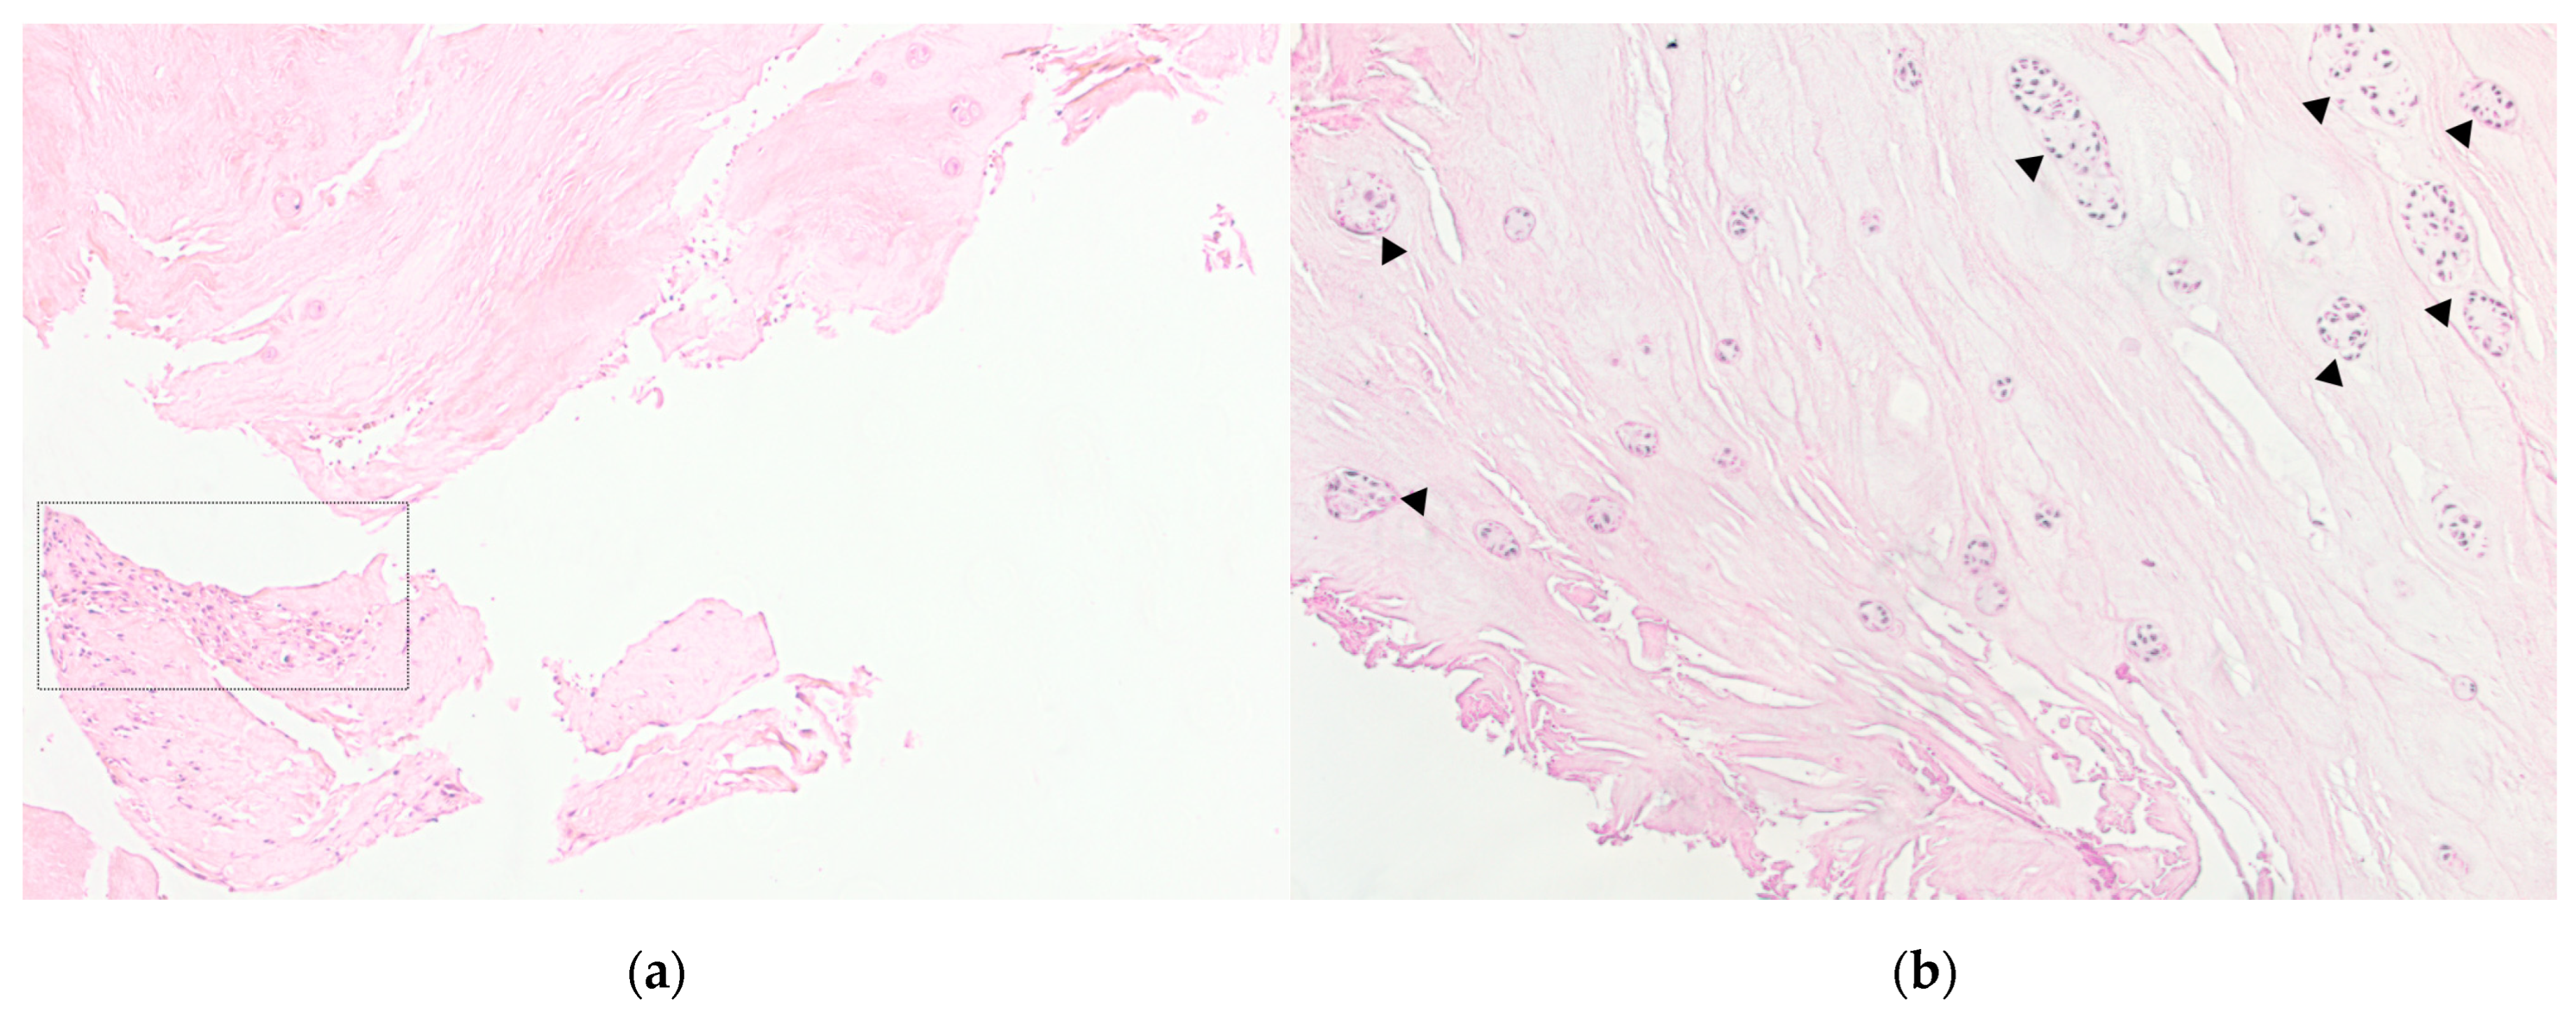

In the IVD samples of the DDD group, inflammatory infiltration zones were identified, combined with vascularization (see Figure 2A) and the presence of granulation tissue. There were also the regions of hyaline cartilage with inflammatory cells infiltration.

Figure 2.

Patient intervertebral disc sample obtained as a result of microdiscectomy in the patient in her 40 s, with a hernia of the L5/S1 vertebrae. Own data, 2020. Hematoxylin–eosin staining. (a). Light microscopy, magnification 100×. Zones of inflammatory infiltration, combined with vascularization and granulation tissue. (b). The sample of the same patient, magnification 100×. Clusters of nucleus pulposus cells (triangles) are a characteristic sign of disc degeneration.

The morphological degeneration stage in the samples of the control group was Me = 1.000 [0.000–3.000] points, while of the DDD group was Me = 7.000 [6.000–10.000] (p < 0.0001). In the samples of DDD patients, clusters of NP cells (clusters of chondrocytes) were detected (see Figure 2B), especially in damaged areas that were absent in the control samples, which can be regarded as another morphological sign of disc degeneration. The average area of chondrocyte cluster was 3645.393 ± 551.701 μm2 and the average number of cells in them was 9.411 ± 3.382.